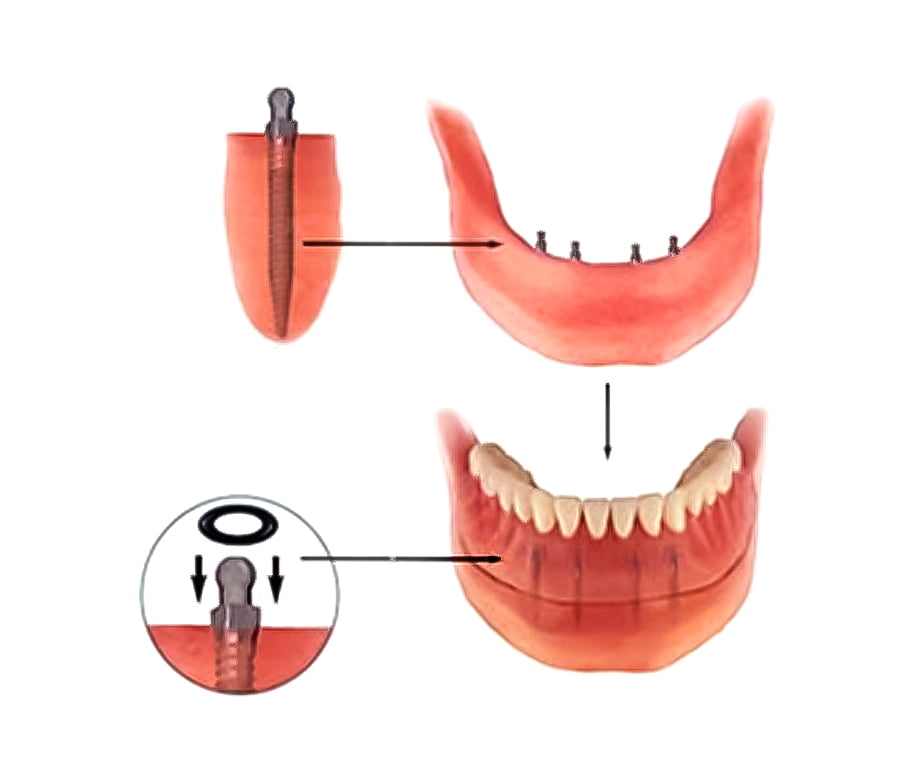

Mini-implanturile dentare sunt mai inguste decât implanturile obișnuite. Acestea sunt utilizate în anumite cazuri în locul implanturilor normale, din motive medicale, financiare sau anatomice. Cel mai frecvent sunt folosite pentru dinții mici, dinții din față, premolarii, dinții din zone înguste sau pentru pacienții la care densitatea țesutului osos este scăzută. Susținând majoritatea tipurilor de dinți de înlocuire, mini implanturile sunt folosite pentru proteze semimobile, punți și coroane fixe. Diferențele dintre mini-implanturi și implanturile obișnuite: Dimensiune – Diferența de dimensiune constă în diametrul implantului. Mini-implanturile dentare măsoară mai puțin de 3 mm în diametru, în timp ce implanturile obișnuite măsoară 3,5-5 mm. Rezistența – deoarece mini-implanturile sunt mai mici, nu pot suporta forța de masticatie pe care o poate suporta un implant obișnuit. Din acest motiv, acestea nu sunt folosite în cazul în care se înlocuiesc molarii. Procesul de vindecare – procesul de încorporare a unui mini-implant dentar este mai rapid decât cel al unui implant tradițional. Acest lucru este valabil și pentru timpul de vindecare.